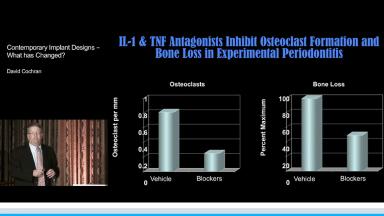

This presentation discusses the evolution of dental implant designs and the effects of various designs on peri-implant tissues. The biologic width around natural teeth is compared to the biologic width around implants. The main contemporary implant systems and types are discussed, and sound research is presented to explain the current understanding of dental implant components and macro designs. Butt joint, tissue level, and platform switching designs are compared, as well as external hex and internal conical implant-abutment connections. Biologic effects of different designs are presented, and clinical advice based on basic research is given at the conclusion.

- recognize the effect of dental implant designs and components on the surrounding tissues

- explain the soft and hard tissue response to different implant designs